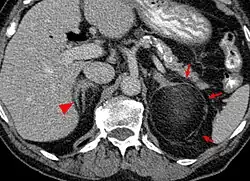

| An adrenal myelolipoma | |

Most myelolipomas are unexpected findings on CT scans and MRI scans of the abdomen. They may sometimes be seen on a plain X-ray films.[4]